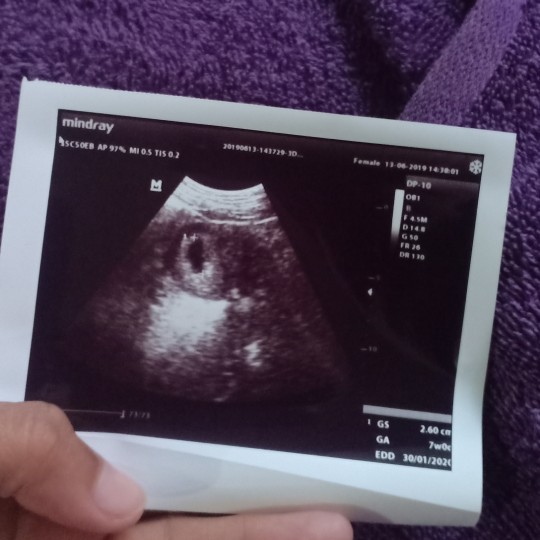

Saya telat 1bln lebih ini hasil Usg nya bunda